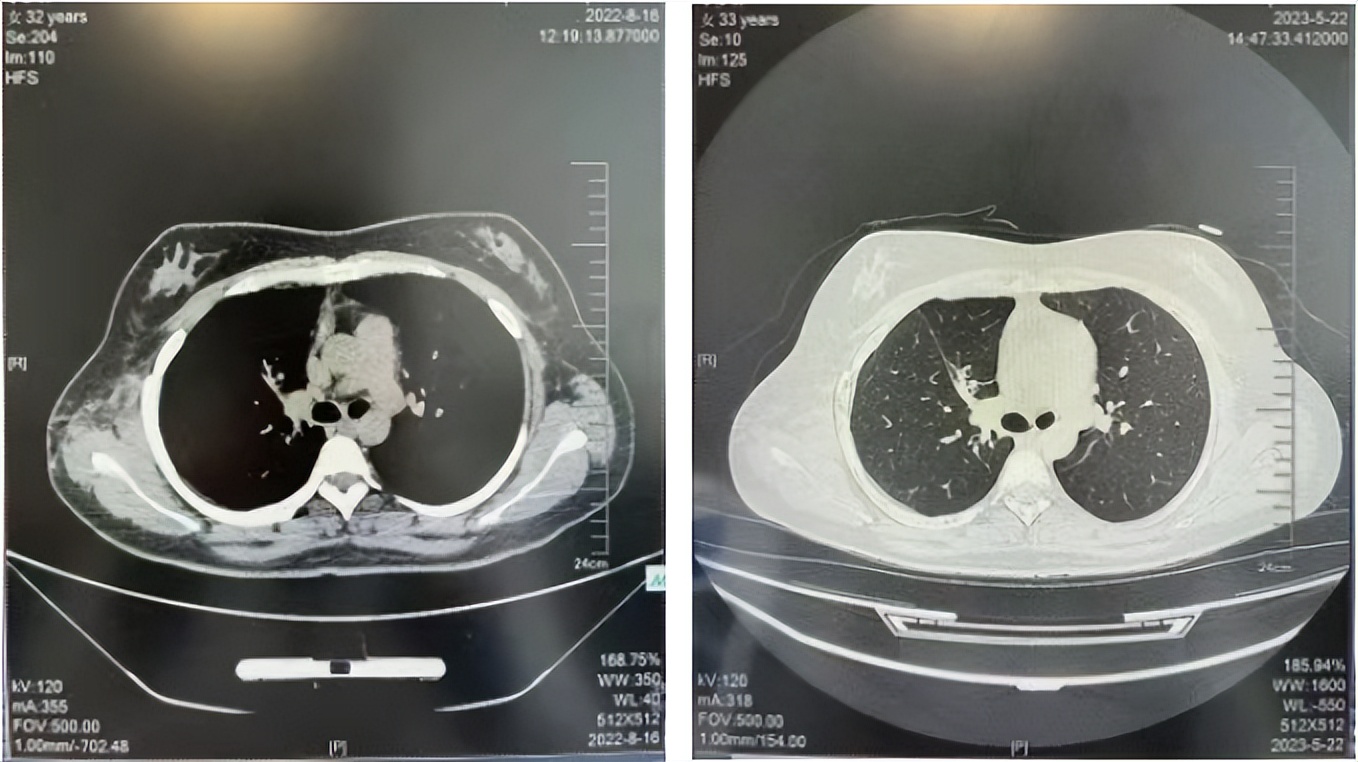

56岁,女性,无吸烟史饮酒史,既往体健。2023年02月患者体检发现肺占位性病变,胸部增强CT:右肺下叶后基底段结节;右侧锁骨上及纵隔内多发淋巴结肿大。PET-CT:右肺下叶周围型肺癌可能性大;1R、2L、3P、4R、4L及7组淋巴结转移可能性大。2023年02月就诊于本院胸外科行超声胃镜下纵隔肿物穿刺活检术,病理:结合免疫组化,符合肺腺癌。行NGS基因检测:EML4:exon20-ALK:exon20融合。PD-L1(克隆号22C3)TPS=55%。

临床诊断:右肺下叶恶性肿瘤cT1bN3M0,IIIB(第9版分期),纵隔淋巴结继发恶性肿瘤,锁骨上淋巴肿继发恶性肿瘤

治疗经过:2023年3月27日始行恩沙替尼靶向治疗至今,最佳疗效为PR,末次评效为维持PR。期间出现轻度肝功能异常(DILI 1级),对症处理后好转。截止目前PFS为26个月。

2023年2月20日基线检查

2024年6月复查PR(最佳疗效)

2024年12月复查维持PR

2025年3月复查维持PR